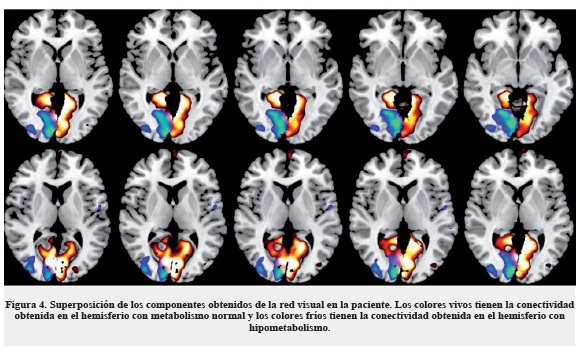

De los resultados del ICA se seleccionan los componentes relacionados con redes funcionales, siguiendo la metodología propuesta en la literatura (24), y entre las redes funcionales se extraen aquellas que se encuentran en áreas visuales. La Figura 3 muestra la red funcional visual obtenida en siete individuos sanos (6 mujeres, promedio de edad = 35 años). Se puede observar la distribución simétrica en ambos hemisferios de la actividad sincrónica.

Para la paciente en mención, la red visual se divide en dos componentes (Figura 4): uno que captura la mayor parte de la actividad en el hemisferio izquierdo, colores vivos en la figura, y el segundo (con colores fríos en la figura), que captura la mayor parte de la actividad en el hemisferio derecho, en la región donde se ha detectado el hipometabolismo con PET. La figura muestra cómo la unión de estas dos redes conforman la red visual vista en controles. También se observa que la red en el hemisferio derecho tiene mayor extensión que el hipometabolismo observado en el PET (Figura 5).